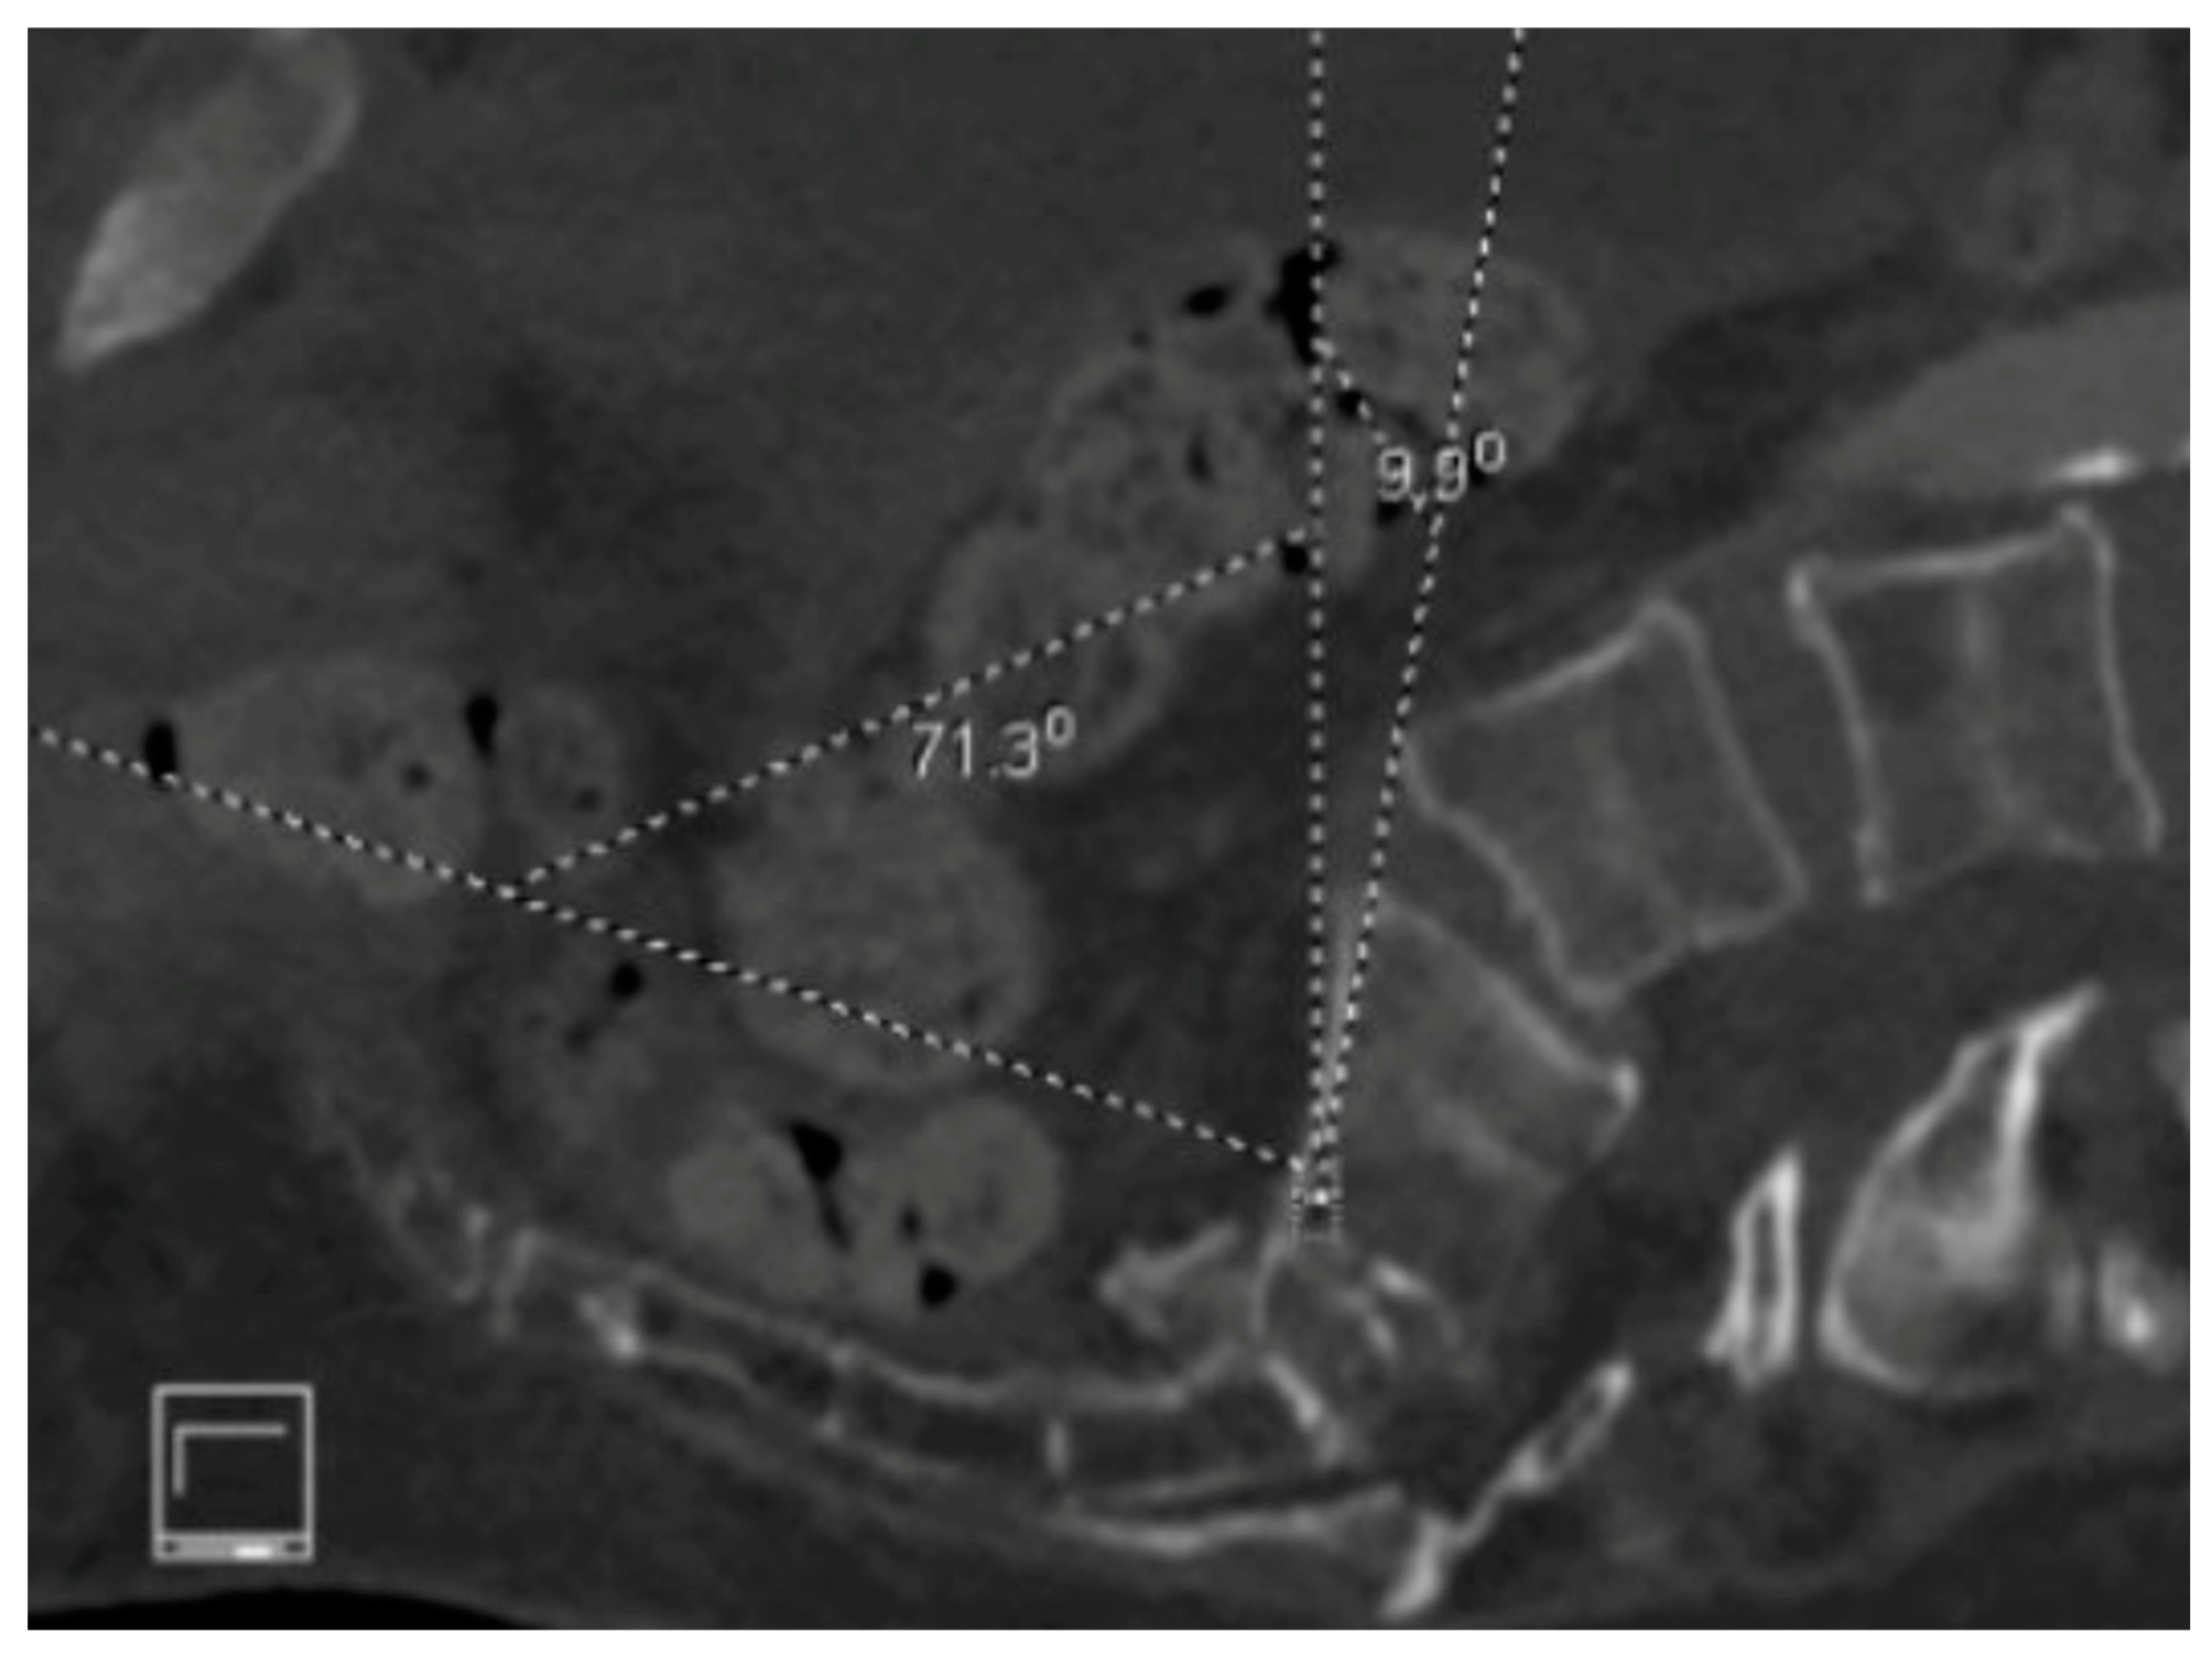

6. Spinopelvic Fixation Percutaneous Technique

7. Tran-Sacral Percutaneous Technique